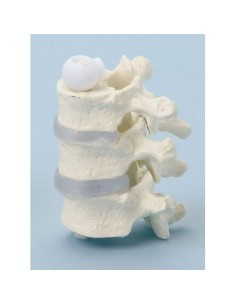

Colonne lombaire 3B Scientifique avec hernie discale dorsolatérale A76/5

3B Scientifique, Colonne vertébrale de luxe peinte de façon classique avec troncs de...

Du crâne en 22 parties à verrouillage magnétique aux modèles de colonne vertébrale, des modèles d'articulation aux modèles de cœur, chaque pièce de notre collection est conçue pour une immersion totale dans l'étude de l'anatomie humaine. Nos modèles, réalisés à partir de scans d'os réels, garantissent une expérience tactile authentique et une fidélité de poids presque identique aux originaux.

Indispensables aux étudiants comme aux professionnels, nos modèles anatomiques sont des outils pédagogiques qui permettent d'observer les structures anatomiques avec précision, en évitant les dissections ou les études invasives. Ils sont également utiles pour expliquer les pathologies aux patients, ce qui rend la communication plus efficace et permet de gagner un temps précieux.